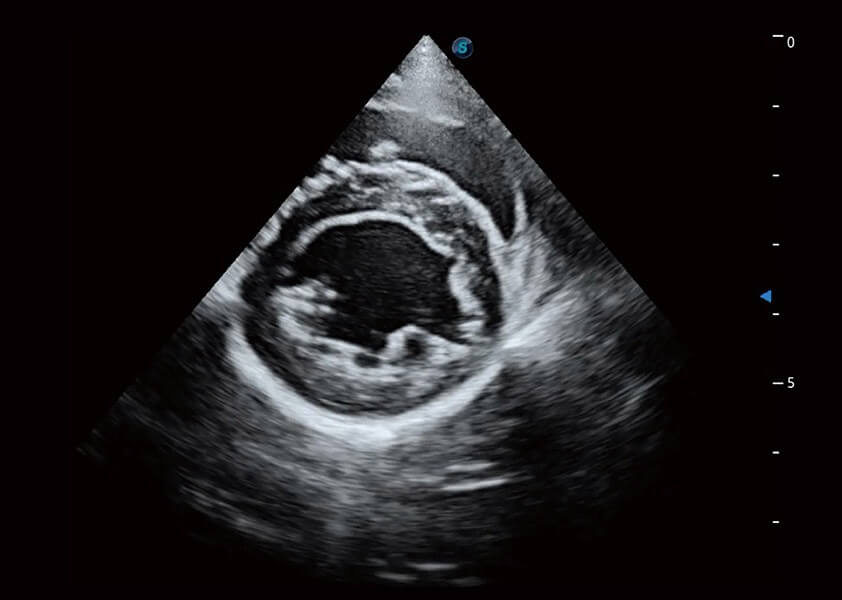

ProPet 60 作为一款高端台式动物超声设备,为动物医生的日常诊断提供了一系列贴合动物临床需求、解决临床实际问题的高级成像功能。凭借全系列高清探头,满足医生对腹部、心脏、生殖、浅表、肌骨等成像的所有需求,切实帮助您提升检查效率,提高诊断信心。

动物是人类最亲密的朋友和最值得信赖的伙伴。milan米兰也一直致力于探索动物专用的超声影像解决方案。 全新推出的ProPet系列,是milan米兰在动物超声影像智能化、专业化、精准化的一次跨越式革新。动物不能用言语来表述自己的不适,通过超声影像,ProPet系列搭建了动物医生与不同物种沟通的“桥梁”,为动物医生注入了“治愈之力”。